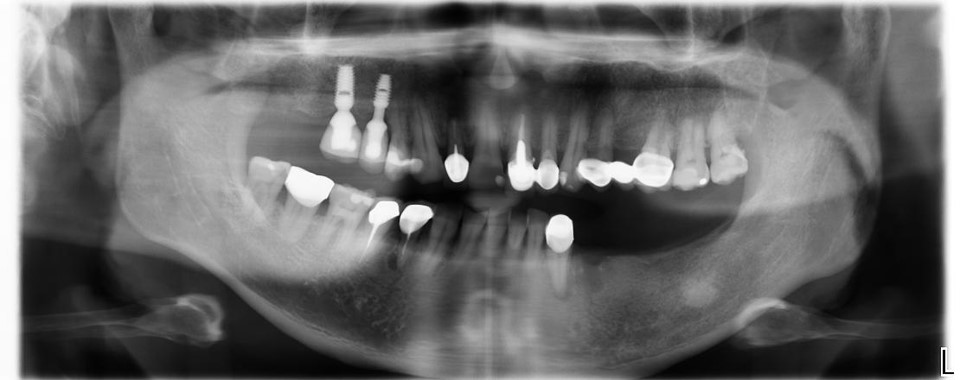

▲(治療前,左下骨高度足夠)

▲用X光看反而缺牙缺的更嚴重,看來我家人平常的口腔護理習慣的真的很差

治療前,左下骨高度足夠

植體植入後X光確認:#34-37

治療後X光:#33-37